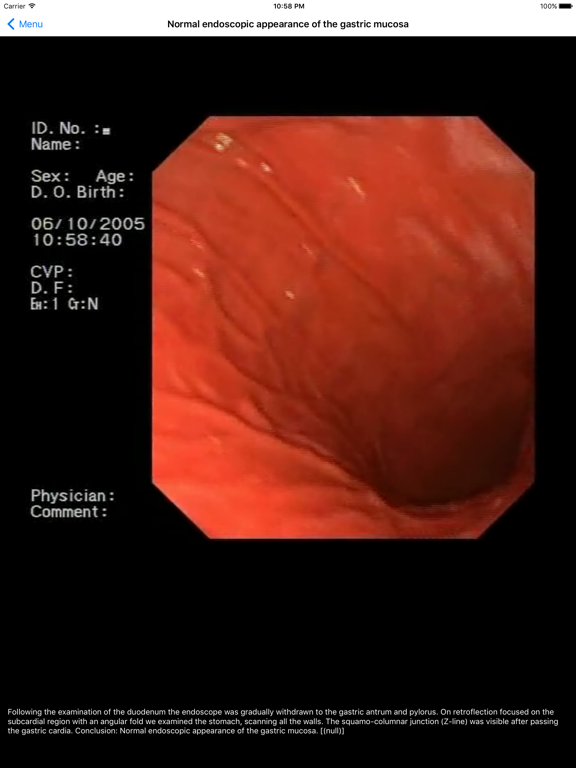

This app is a Lite version of ENDO3® Atlas of Gastrointestinal Endoscopy, endo3®GI project (ISBN 80-969617-0-5) - reference/learning tool for gastroenterologists, surgeons, internists, and other physicians evaluating endoscopy for diagnosis of gastrointestinal disease.

Authors: Assoc. Prof. Radan Keil, M.D., Ph.D., Jan Stovicek M.D.

GI Endoscope Laboratory, Department of Internal Medicine, Motol Hospital, 2nd Medical Faculty, Charles University in Prague, Czech Republic